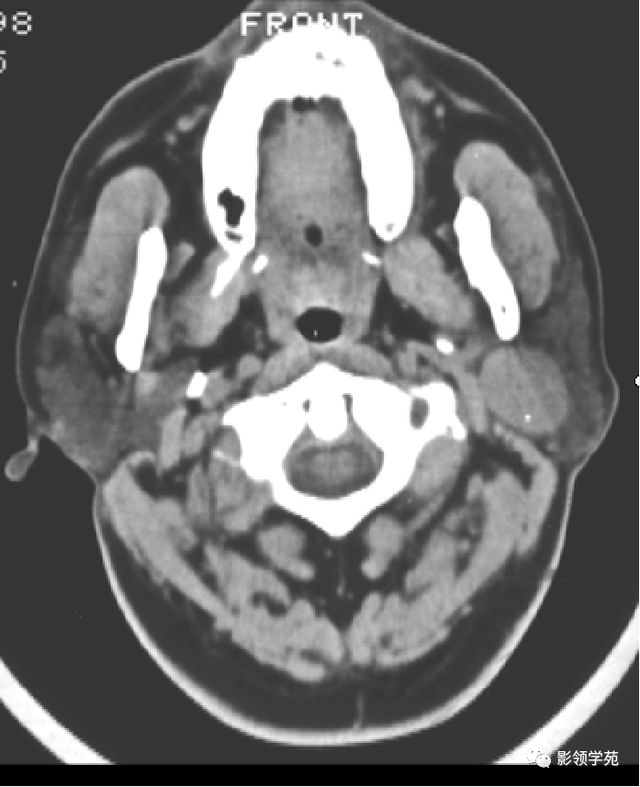

腮腺内外肿块的定位:

腮腺肿瘤外缘与腮腺之间有无脂肪层存在;

肿瘤较大时凭证 茎突推压的偏向及肿瘤最大径;

腮腺深叶肿瘤与咽旁间隙肿瘤判别 :

腮腺深叶肿瘤多呈哑铃状,病变常致茎突和下颌支之间的距离增宽,咽旁间隙脂肪带常内移;二腹肌后腹后移。

咽旁前间隙的肿瘤常致咽旁脂肪带外移,在肿瘤和腮腺深叶间有脂肪距离 ,病变致其茎突下颌沟增宽少见。

咽旁后间隙肿瘤致二腹肌后腹前移。